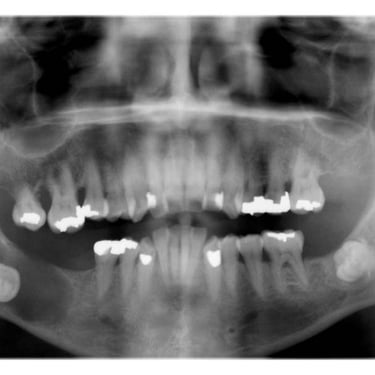

Dientes impactados

Los dientes impactados son dientes que no pueden erupcionar correctamente debido a la falta de espacio o a una obstrucción.

Los pacientes pueden notar que un diente no ha salido, aunque debería haberlo hecho. Esta condición es común con las muelas del juicio y los caninos superiores.

El tratamiento puede incluir la extracción del diente impactado o la creación de espacio para permitir su erupción.